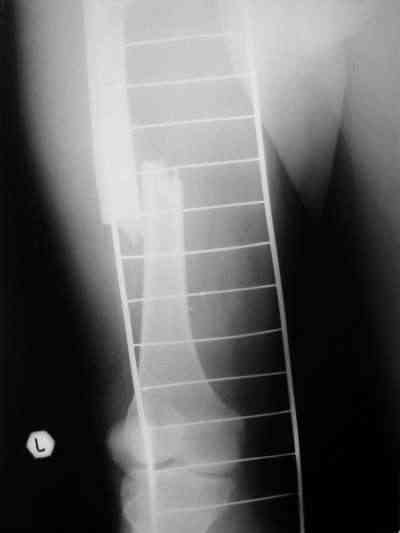

Снимки в приложении.

Конечно, при современном подходе, применение PFNa удленной версии со спиральным лезвием было бы адекватным решением. А также еще далеко до малоинвазивной техники, представленной А.Ю.Семенистым в издании Margo Anterior (МАТИС и AO/ASIF), где выполняется имплантация DHS через 4 сантиметровый разрез, снимаю шляпу перед этими мастерами, просто - высший класс, но ... какие наши годы!! ;-)

В приложении и имеющийся в наличии брейс. Приношу извинения за низкое качество снимков.